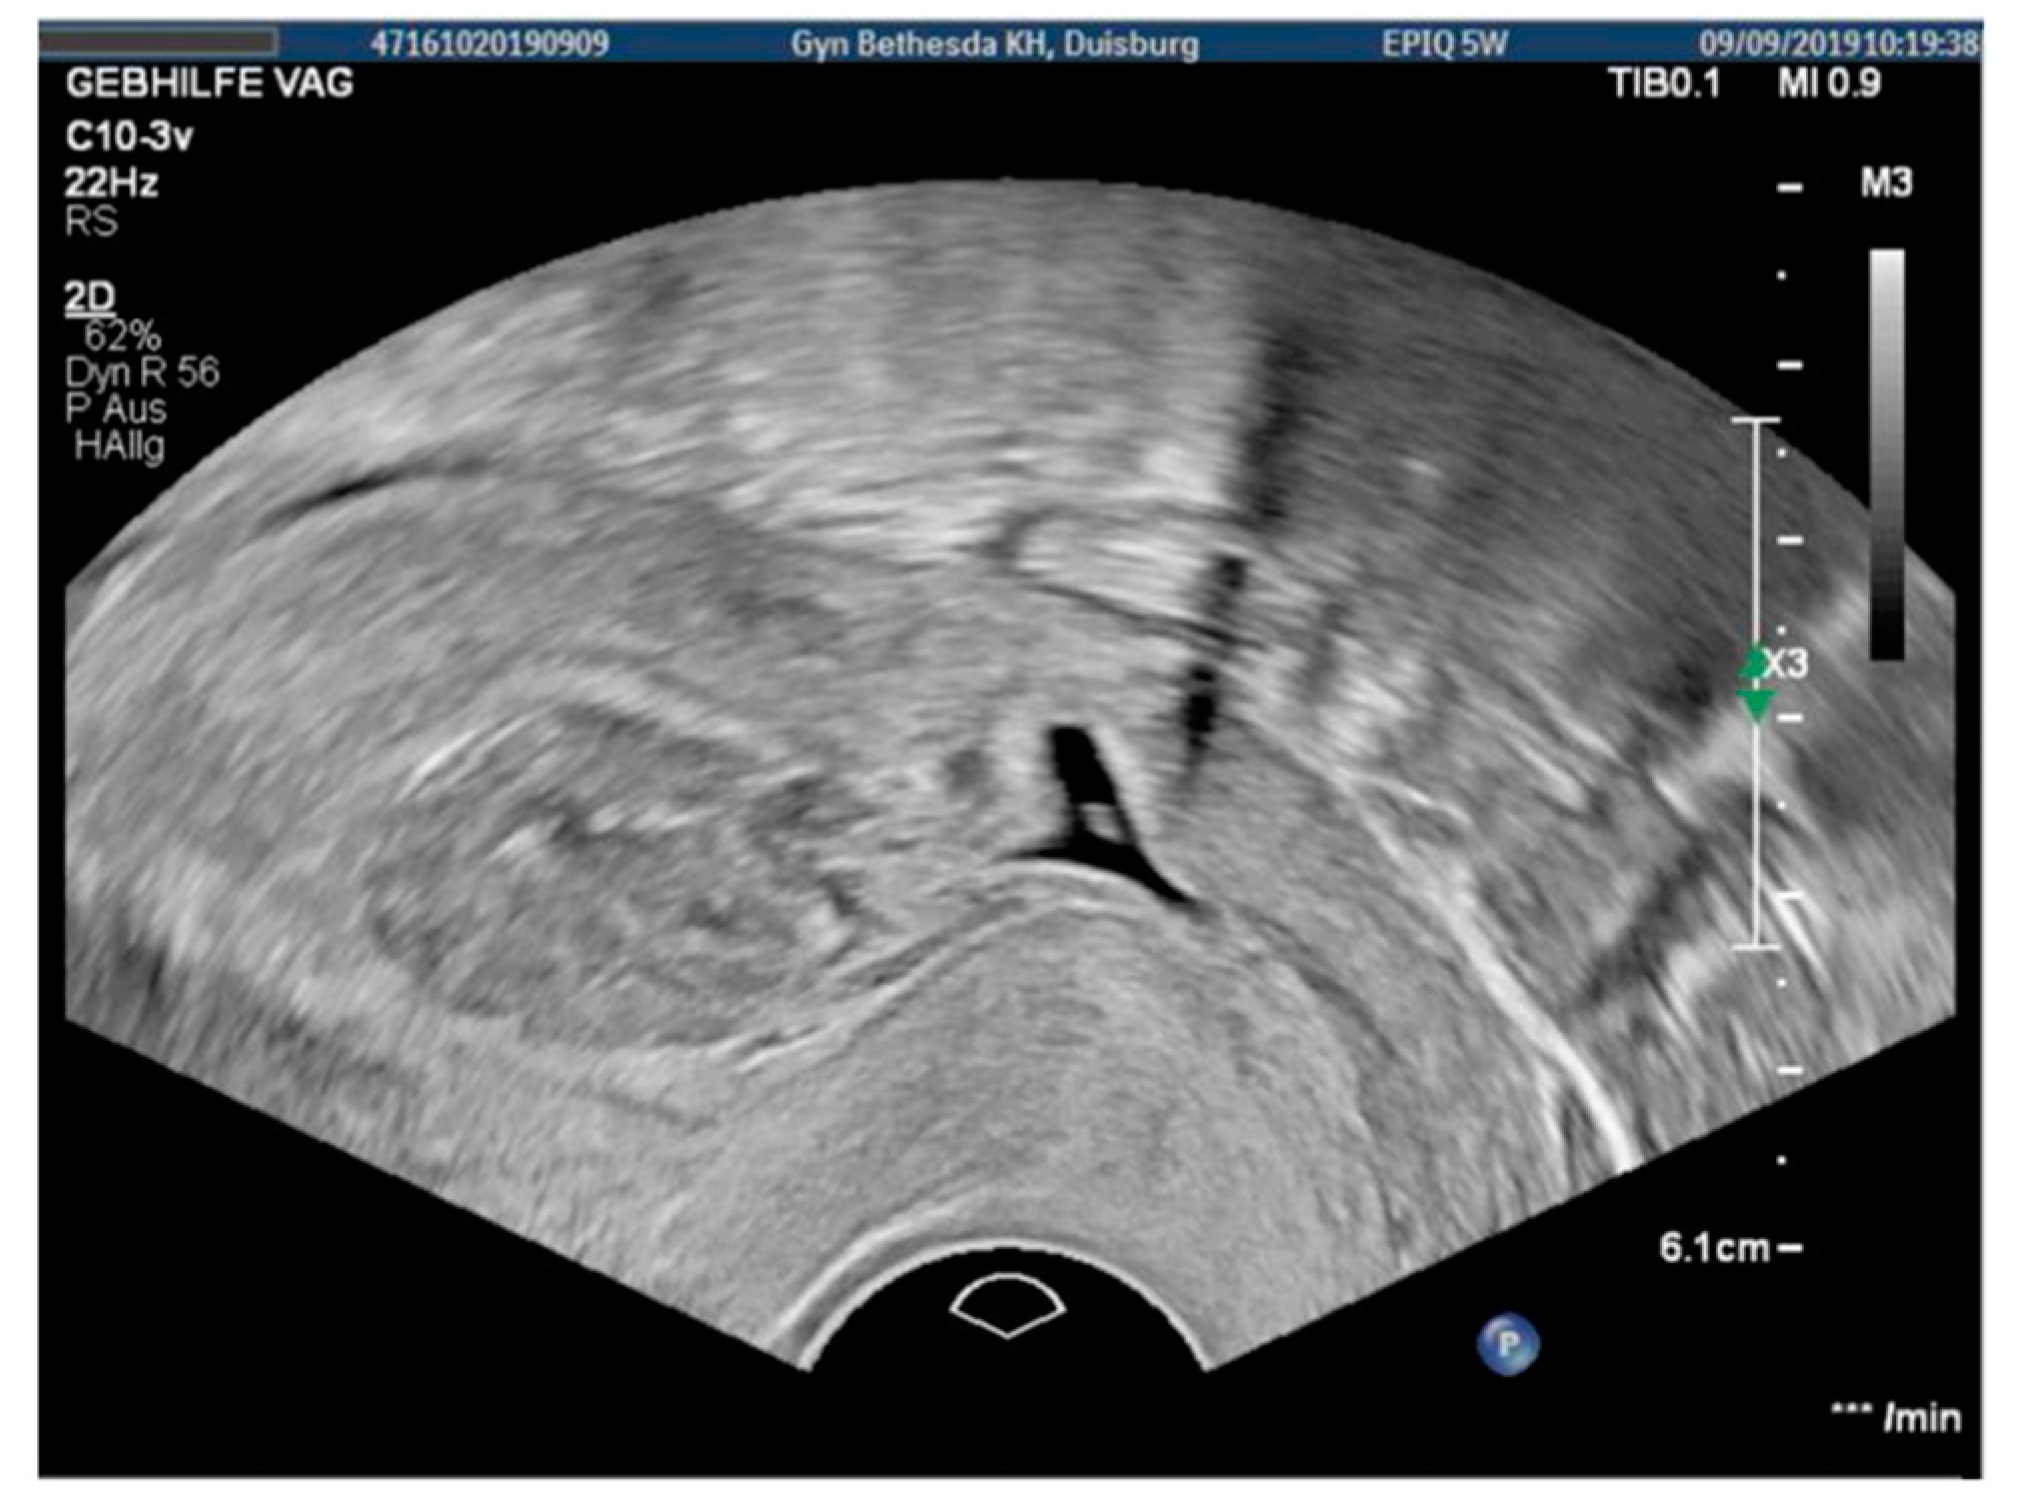

3.2. Case 2—Niche Pregnancy—Combined Hysteroscopic and Laparoscopic Treatment